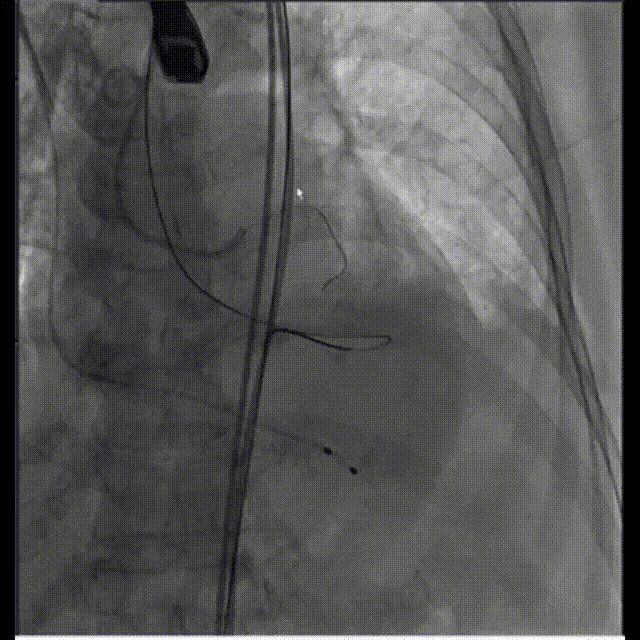

冠脉风险评估

冠脉遮挡,LM植入支架

冠脉灌注良好,确认人工瓣膜位置